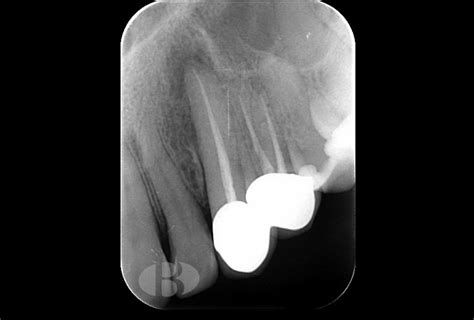

La radiografía periapical permite el análisis de estructuras como la corona, raíz dentaria y periápice, ofreciendo una visión más específica de un diente o región en particular. Presenta una alta sensibilidad, principalmente en la región anterior. Sin embargo, todavía existe dificultad en el diagnóstico debido al espesor de las corticales óseas y las estructuras anatómicas superpuestas sobre las raíces, generando “ruido anatómico”.

La distorsión geométrica en las radiografías periapicales, puede resultar en un aumento o disminución del tamaño de las lesiones, resultando muchas veces en la incapacidad para visualizarlas. Por tanto, existen varios factores que reducen la capacidad diagnóstica de la radiografía periapical convencional por representar una imagen bidimensional de estructuras tridimensionales.

Radiografía dental mostrando un absceso periapical